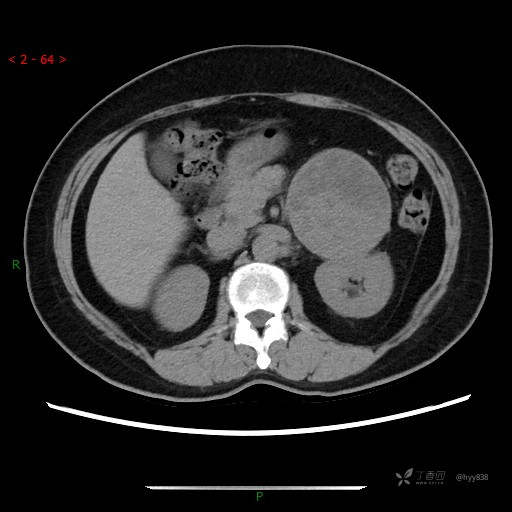

增强静脉期